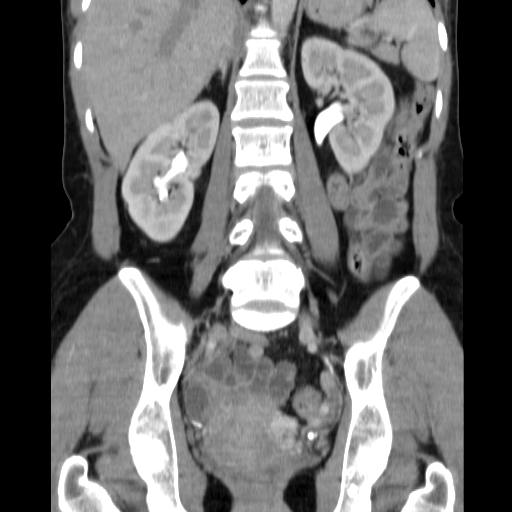

CT-urografi af normale nyrer